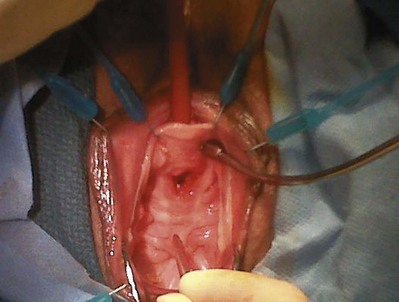

Sterile 0.9% normal saline is injected into the vaginal epithelium, surrounding the urethra to provide hydrodistention and aid in tissue dissection. The authors prefer an inverted-U–shaped incision because it enables adequate exposure to the urethra and bladder and access to the endopelvic fascia and subsequent retropubic space (Fig. 73–2). The top of the incision is approximately 2 cm below the urethral meatus (easily visualized with assistance of an Allis clamp placed immediately below the meatus), and the arms of U should extend to the level of the bladder neck (determined by Foley balloon location). A No. 15 blade knife is used to carry this incision down through the vaginal epithelium, with care to stay above the periurethral and pubocervical fascia (to avoid bleeding and injury to the urethra and bladder). With an Allis clamp and Metzenbaum scissors, thick vaginal epithelial flaps are created. The flaps are retracted with the help of the vaginal ring retractor. Once adequate lateral flaps have been created and the ischiopubic rami are easily palpated, it is appropriate to perforate the endopelvic fascia. It is imperative that the bladder is adequately drained before this maneuver and before later passage of Stamey needles or larger clamps to prevent inadvertent bladder perforation. With the tips of the Metzenbaum scissors pointed upward and to the ipsilateral shoulder, the endopelvic fascia is perforated by remaining directly medial and immediately under the ischiopubic ramus at the superior margin of dissection (Fig. 73–3). Perforation occurs in a superolateral direction, and the dissecting scissors are spread widely to aid in dissection. With the use of blunt finger dissection, the retropubic space is dissected bilaterally (Fig. 73–4). This dissection leads to the connection between the infrapubic and retropubic dissection planes. Simultaneous finger palpation from abdominal and vaginal incisions should be possible, while gently palpating the bladder medially. Aggressive medial mobilization should not be attempted because it may result in bladder injury. Hemostasis should be achieved with bipolar cautery. In the case of women who have undergone prior urethral suspension or sling, more aggressive dissection may be required. The dissection plane into the retropubic space should be immediately adjacent to the periosteum of the pubis, and the dissection should be performed only sharply to minimize risk of injury to the pelvic viscera.